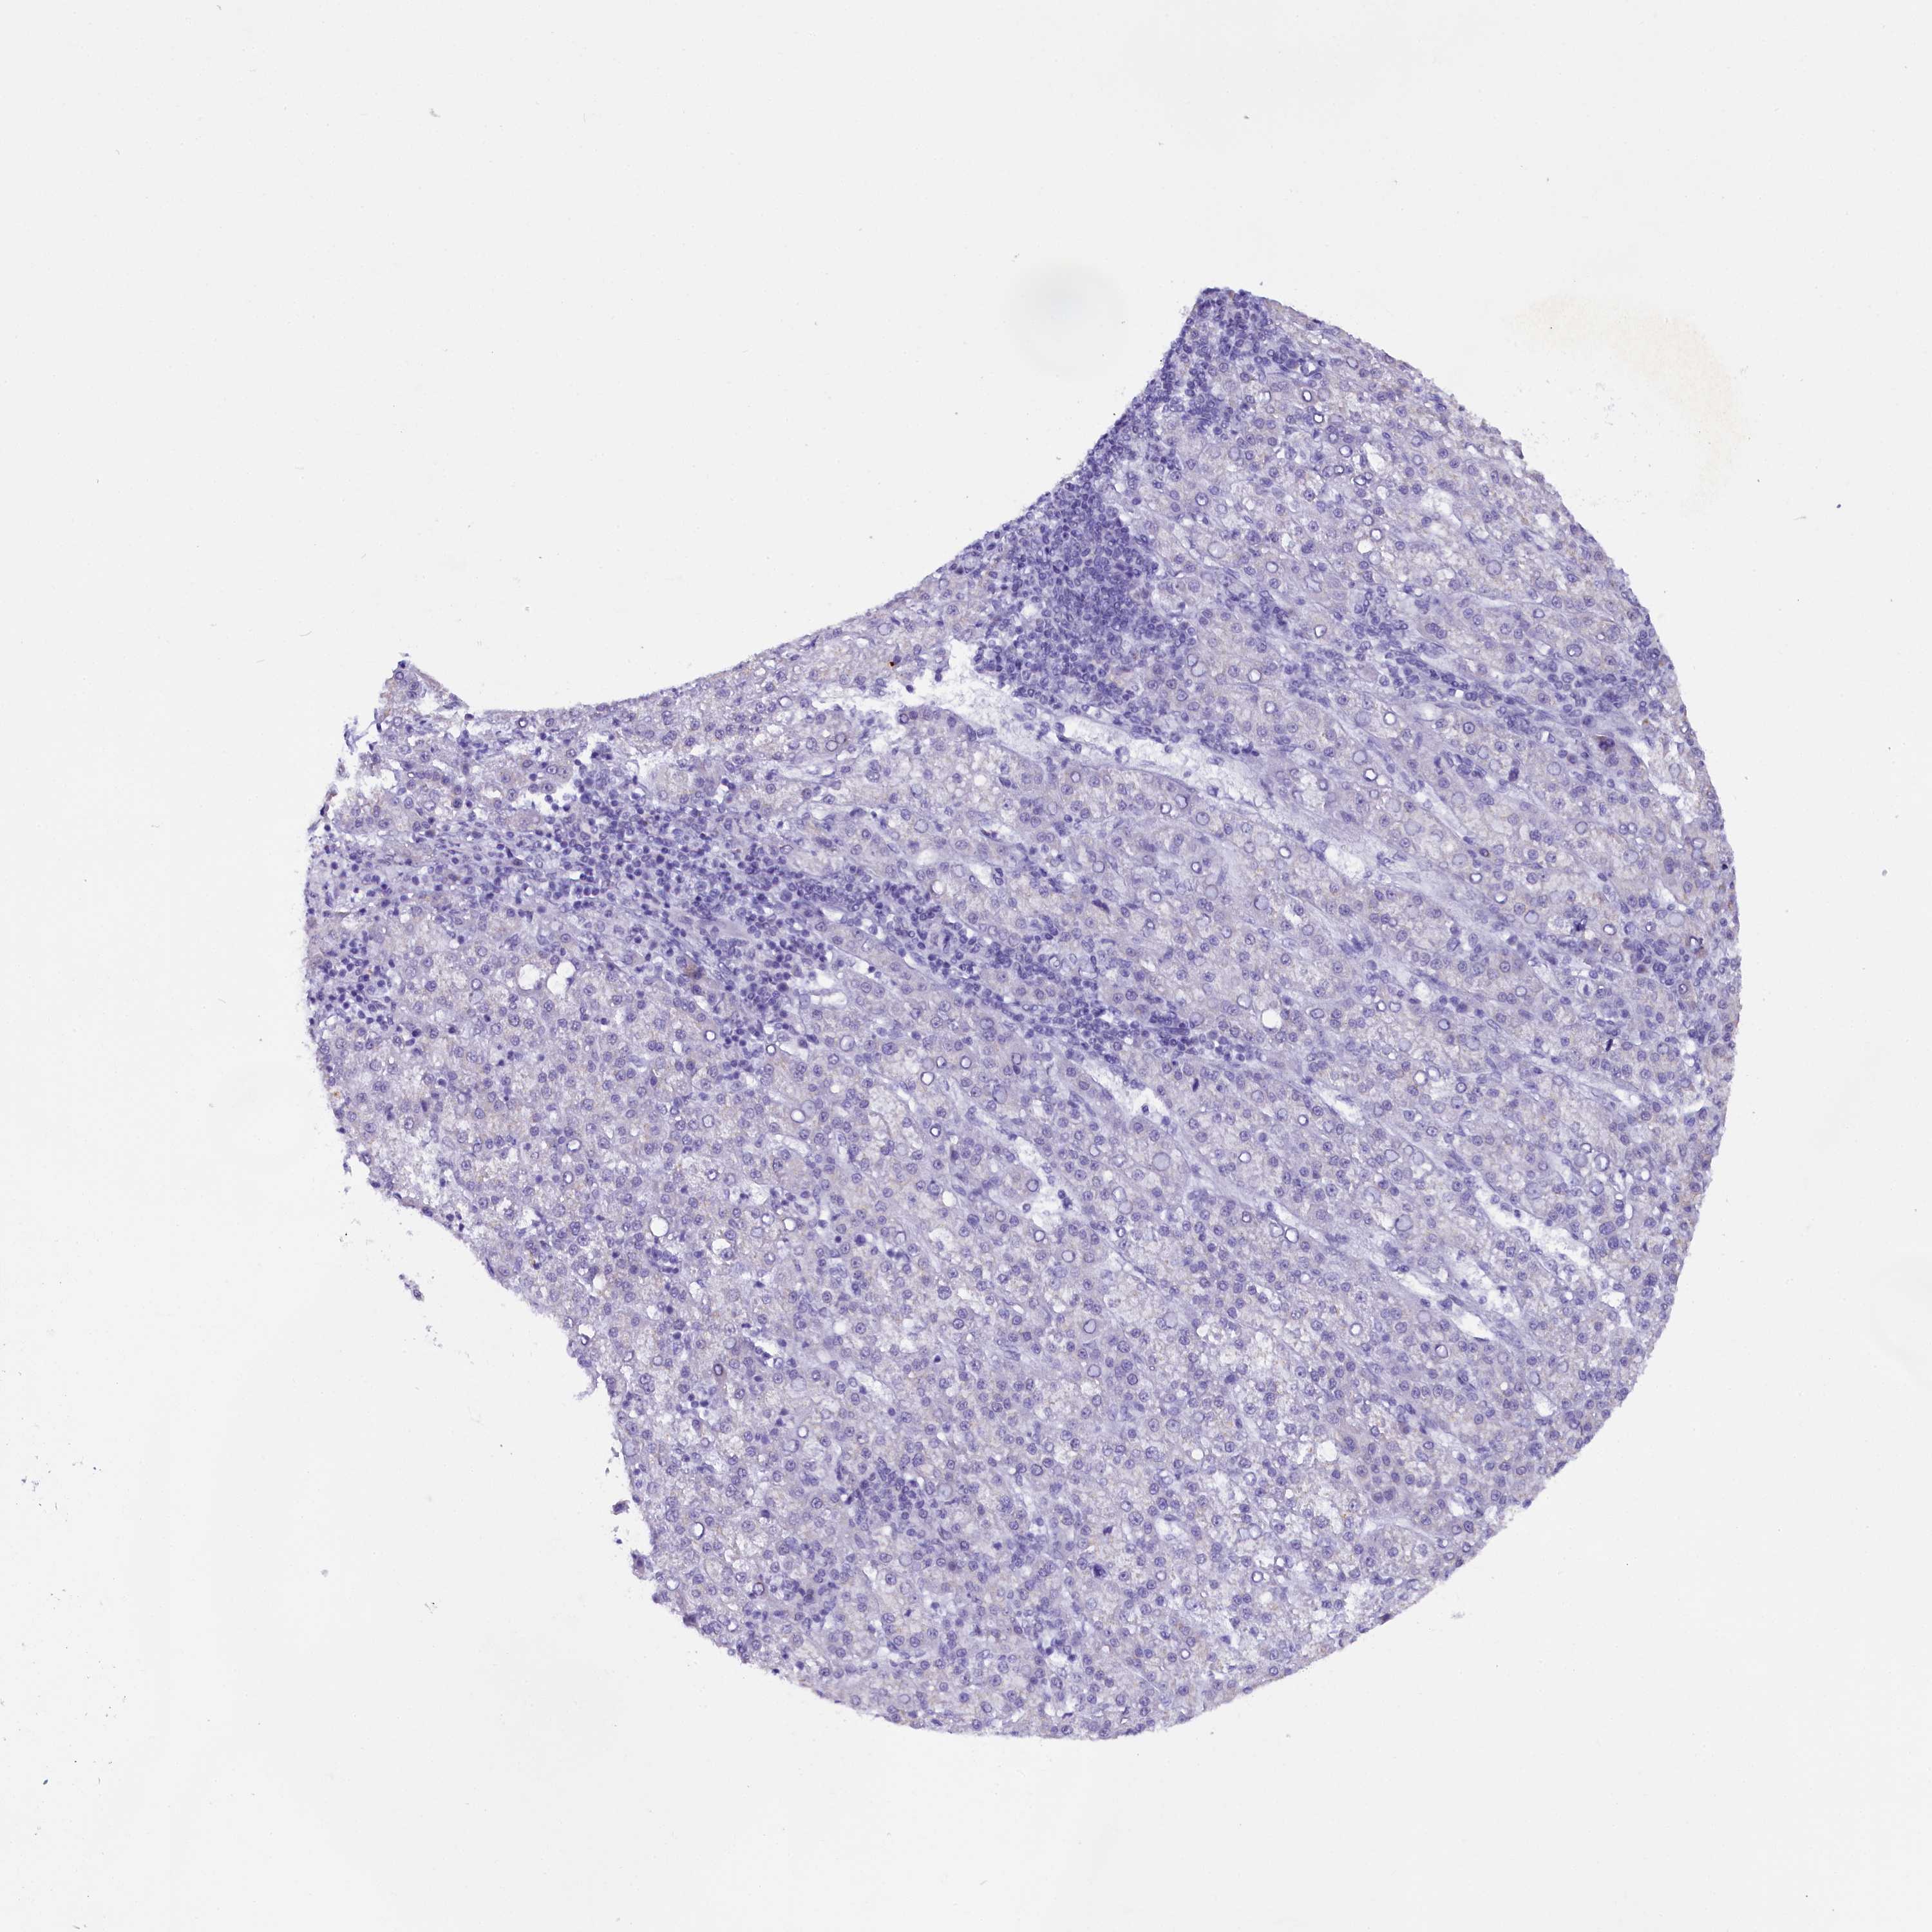

LIVER CANCER - Protein expressioni

A mouse-over function shows sample information and annotation data. Click on an image to view it in a full screen mode. Samples can be filtered based on level of antibody staining by selecting one or several of the following categories: high, medium, low and not detected. The assay and annotation is described here.

Note that samples used for immunohistochemistry by the Human Protein Atlas do not correspond to samples in the TCGA dataset.

Antibody stainingi

Antibody staining in the annotated cell types in the current human tissue is reported as not detected, low, medium, or high, based on conventional immunohistochemistry profiling in selected tissues. This score is based on the combination of the staining intensity and fraction of stained cells.

Each image is clickable and will lead to virtual microscopy that enables deeper exploration of all samples and also displays staining intensity scores, fraction scores and subcellular localization as well as patient and tissue information for each sample.

Antibody HPA042411

Antibody HPA049031

Staining

High

Medium

Low

Not detected

Intensity

Strong

Moderate

Weak

Negative

Quantity

>75%

75%-25%

<25%

None

Location

Nuclear

Cytoplasmic/membranous

Cytoplasmic/membranous,nuclear

Cholangiocarcinoma

Carcinoma, Hepatocellular, NOS